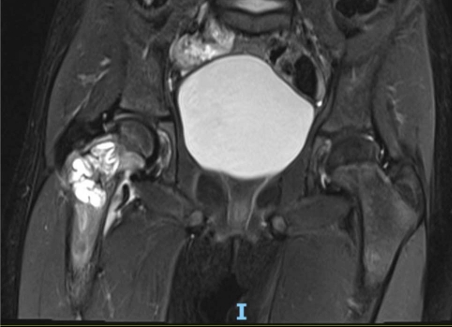

一名 5 岁女童因右下肢外伤后 3 周出现右髋疼痛并伴有跛行而就诊于我院急诊科。体格检查发现,其右髋存在疼痛,且在髋关节旋转时疼痛加重。影像学检查显示,右侧股骨颈可见一大型溶骨性病变,向转子区延伸,并伴有股骨颈应力性骨折及内翻移位(图 1 和图 2)。